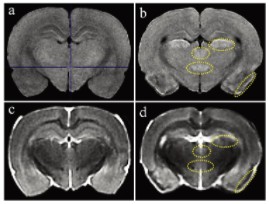

圖1顯示了T1和T2加權(quán)MRI圖像。與對(duì)照組相比, 匹羅卡品處理的動(dòng)物在梨狀皮質(zhì)、丘腦外側(cè)核、丘腦室周后核和大腦下丘腦后核的T1加權(quán)圖像顯示出高T1信號(hào)(圖1a和b)。在匹羅卡品處理的動(dòng)物的T2加權(quán)圖像中,與對(duì)照組相比,在梨狀皮質(zhì)觀察到低T2信號(hào),對(duì)應(yīng)于高T1信號(hào)區(qū)(圖1c和d)。其他3個(gè)高T1信號(hào)區(qū)的T2信號(hào)強(qiáng)度與對(duì)照組相當(dāng)(中等強(qiáng)度)(圖1c和d)。

當(dāng)前易于使用的緊湊型小動(dòng)物磁共振成像系統(tǒng)在匹羅卡品誘導(dǎo)的大鼠腦損傷的臨床前毒理學(xué)病理檢查中的適用性。高T1和低T2信號(hào)顯示明顯的組織病理學(xué)神經(jīng)元損傷,盡管組織病理學(xué)檢查更為敏感。